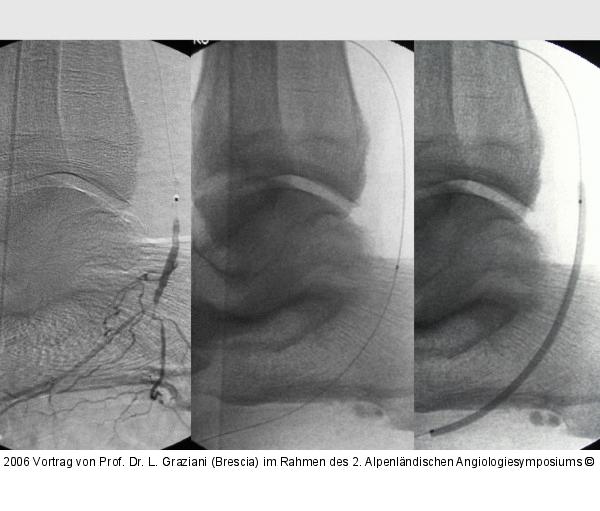

Vortrag von Prof. Dr. L. Graziani (Brescia) im Rahmen des 2. Alpenländischen Angiologiesymposiums

PTA of the foot arteries in diabetics: Extremities Extreme Angioplasty

Abbildung 75: Arteria dorsalis pedis - Katheterisation

Arteria dorsalis pedis - Katheterisation